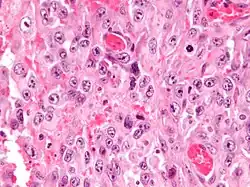

Micrograph of an epithelioid sarcoma. H&E stain.

Histologically, epithelioid sarcoma forms nodules with central necrosis surrounded by bland, polygonal cells with eosinophilic cytoplasm and peripheral spindling.[3] Epithelioid sarcomas typically express vimentin, cytokeratins, epithelial membrane antigen, and CD34, whereas they are usually negative for S100, desmin, and FLI1 (FLI-1).[3] They characteristically lack the protein INI1 (see below). Epithelioid sarcomas typically stain positive for CA125.[4]